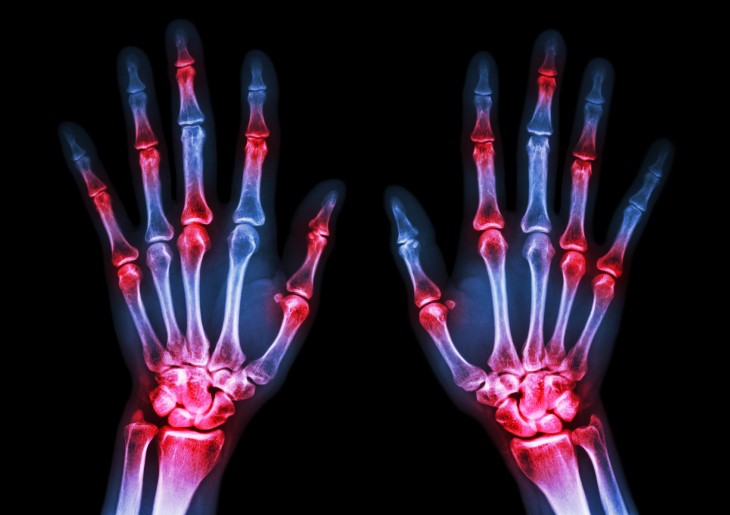

Visible deformities become prominent features of stage 3 RA. Fingers may develop characteristic abnormalities such as swan-neck deformity (hyperextension of certain finger joints), boutonniere deformity (bent middle joint with extended fingertip), or ulnar deviation (fingers drifting toward the pinky side). Knuckles may appear thickened and swollen, and the hands can take on a twisted appearance. These changes often become permanent as the joint structures are irreversibly damaged.

Bone erosion creates gaps and pits in the bone surface, weakening the joint structure. As bones and deformed joints shift position, they can compress nearby nerves, leading to additional pain, numbness, tingling, or weakness in the affected area. For example, wrist damage may compress the median nerve, causing carpal tunnel syndrome symptoms.